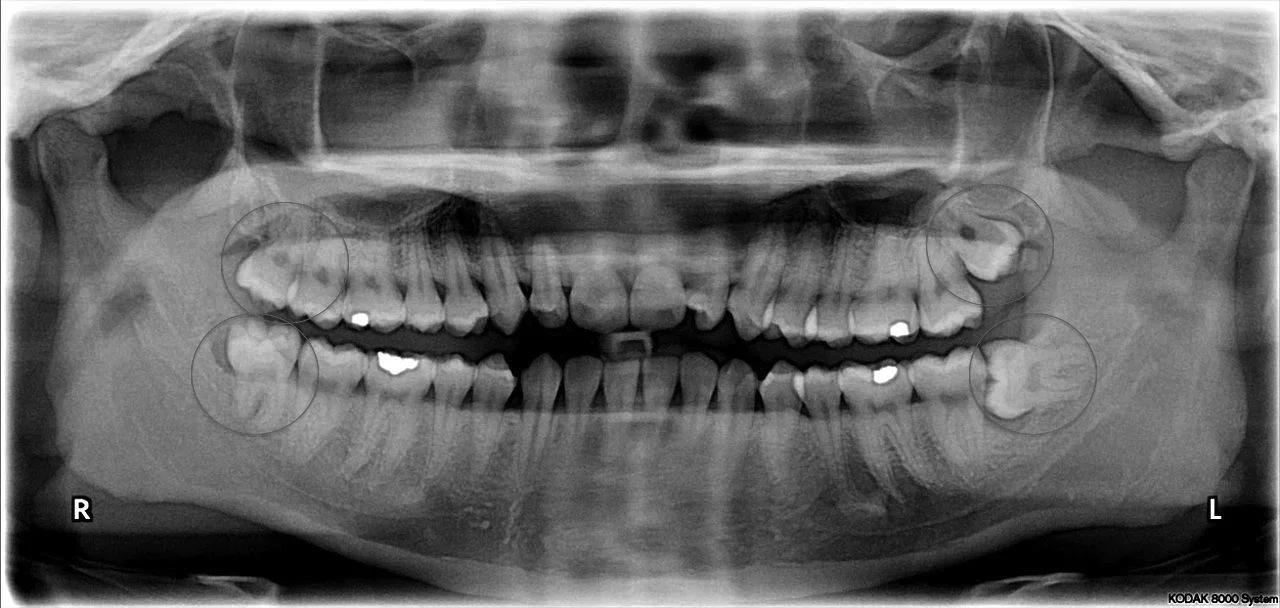

Sometimes wisdom teeth can be a nuisance. Many times we do not even notice them. Usually this depends on how much they erupt - or "come through" into the mouth. Allow me to explain below.....If wisdom teeth are indeed present, they usually do one of three things:

1) Stay un-erupted: As long as the wisdom teeth do not display any pathology or are not harmfully impacted into tooth in front, they can often be left alone.

2) Erupt into occlusion: When there is enough room in the mouth to fit wisdom teeth, they often come into occlusion and can function as another set of teeth.

3) Erupt only partially: When there is not enough room the teeth will often only partially come through. When this happens, they can difficult to keep clean and can be at risk of decay and infection which can come and go. In this case, wisdom teeth may need to be removed!